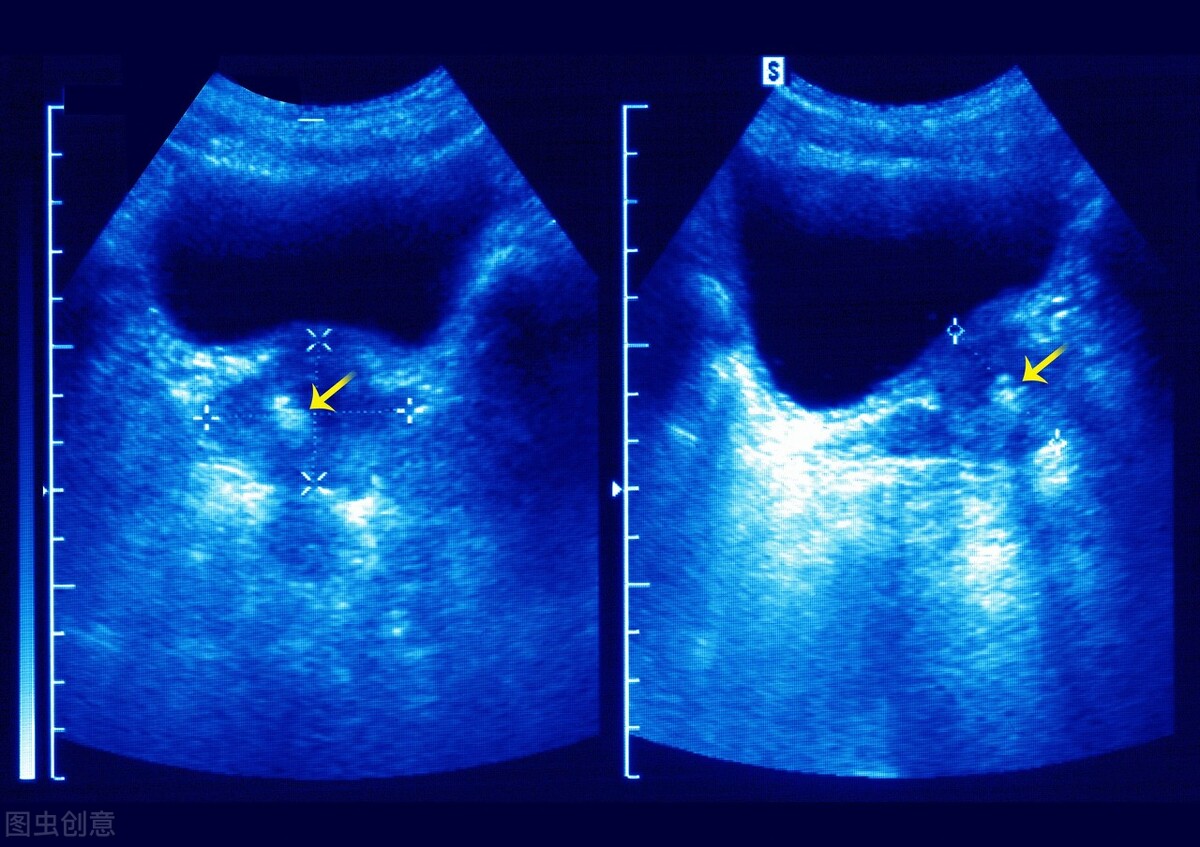

*丸睾**癌早期发展不明显,随着肿瘤细胞的不断增大,出现病侧*丸睾**肿物、沉重、有轻微的肿痛和钝痛等表现。